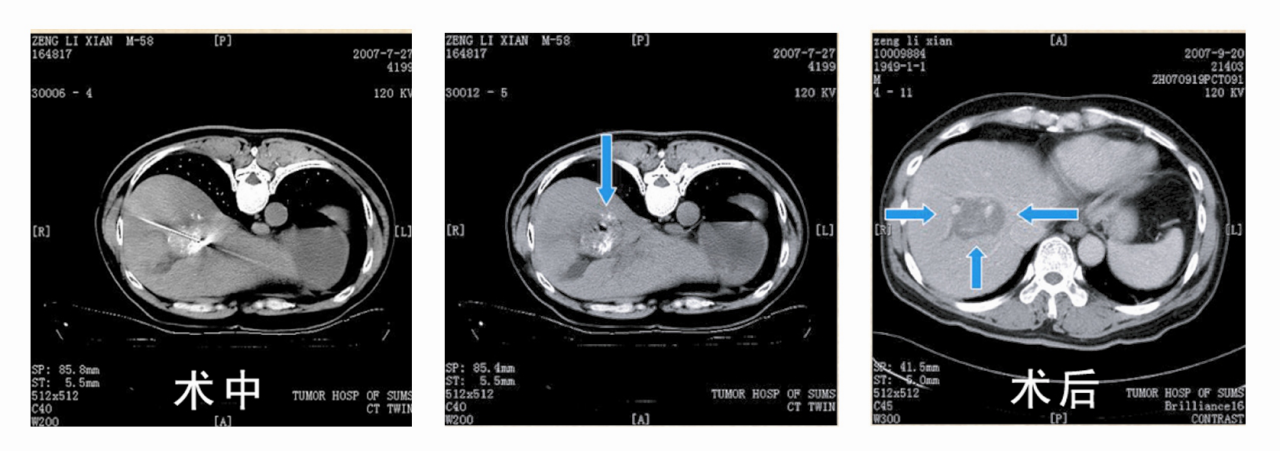

消:内部爆破粉碎肿瘤。消是经皮穿刺消融肿瘤。在影像设备的引导下,将治疗器械经皮穿刺精确定位在肿瘤上,通过化学或物理手段对肿瘤组织进行破坏,从而达到治疗肿瘤的目的。如经皮无水酒精消融:经皮向肿瘤内注射无水酒精,使肿瘤凝固性坏死;经皮射频消融:将射频电极针直接插入肿瘤内,通过裸露的电极针使其周围组织内正负离子在射频电场中产生高速振动和摩擦,继而转化为热能。其热能随时阊逐渐蓄积并向外周传导,从而使局部肿瘤组织发生热变性和凝固性坏死等。

患者:男,58岁,6月确诊为原发性肝癌,进行肝癌微波消融术后病灶基本消失